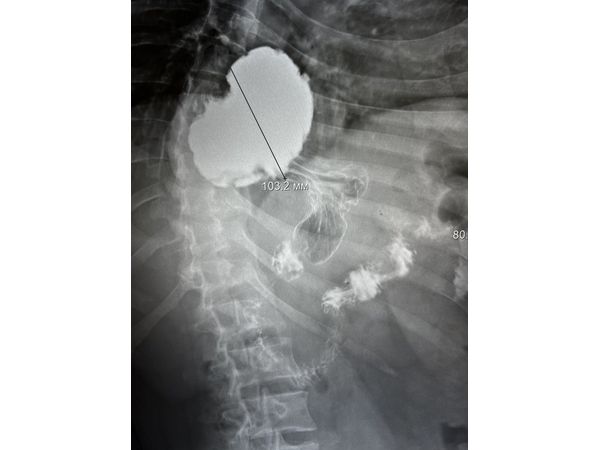

Вместо гастроскопии сделали рентгеноскопическое исследование пищевода, желудка и двенадцатиперстной кишки. По результатам удалось установить, что часть желудка расположена в грудной полости и зафиксирована в заднем средостении (между сердцем и позвоночником). Такое состояние соответствует фиксированной аксиальной кардио-фундальной грыже пищеводного отверстия диафрагмы.

Через месяц провели рентгенконтроль: грыжи не было, желудок расположен правильно (в брюшной полости). Гастроэзофагеального рефлюкса в положении Тренделенбурга (лёжа на спине, ступни немного выше головы) и стоя не выявлено.